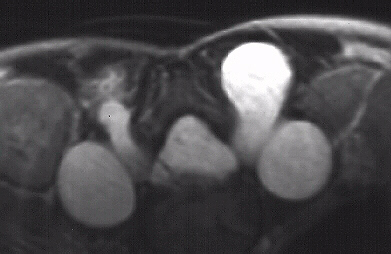

This 7 year old male presented to the cerebral palsy clinic with mild development delay, hyperactivity, and kyphosis. On physical examination he was slightly small for age (5th percentile weight for age, 10th percentile height for age) and had hyperactivity. He had no clonus or spasticity but a slightly clumsy gait. An MRI and plain x-rays were ordered (image 1, 2 & 3). After two years of brace wear the kyphosis increased to 78 degrees(image 4). The child is complaining of the brace and starting to refuse brace wear.

These mass appear to be meningoceles without neurofibroma.